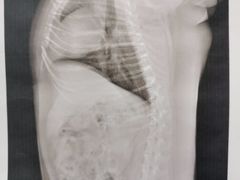

• 爱侣宠医·鹦鹉专科·小型哺乳类·异宠专科(灵石路店)

• 其他(161)»